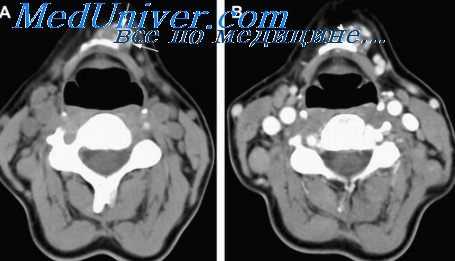

КТ изменения лимфоузлов - дифференциация лимфогранулематоза и неходжкиновских лимфом

Лимфатическую систему изучают по локализации или топографоана-томической принадлежности пораженных лимфатических узлов, их размерам, форме, структуре (однородная, неоднородная), расширению лимфатических стволов, сосудов.

По форме поражения лимфатических узлов выделяют:

1) изолированную форму;

2) образование пакета узлов;

3) формирование конгломерата узлов;

4) лимфоидный инфильтрат.

Изолированной формой поражения являются одиночные увеличенные лимфатические узлы, не связанные между собой.

Группу изолированных лимфатических узлов, тесно соединяющихся между собой, расценивают как пакет. При этом между лимфатическими узлами всегда имеется ткань меньшей плотности.

Конгломератом лимфатических узлов считают объединенные в единое целое узлы с ровными или бугристыми контурами, имеющие, как правило, однородную плотность. Размеры конгломерата различны: от 50 мм до опухоли, охватывающей несколько анатомических групп.

При вовлечении в патологический процесс сальника, перикарда или плевры конгломерат может занимать большую часть брюшной или грудной полости. Главное отличие конгломерата — отсутствие границ между узлами.

КТ тазовых лимфоузлов при лимфогранулематозе (ЛГМ) - болезни Ходжкина

Лимфоидный инфильтрат — патологическая ткань с нечеткими краями, расположенная по ходу лимфатических стволов и крупных лимфатических сосудов.

Выделение различных форм поражения лимфатических узлов имеет важное значение для оценки характера их изменений, контроля за динамикой патологического процесса в ходе лечения, поиска диагностических критериев изменения лимфатических узлов при некоторых заболеваниях. Структуру лимфатических узлов оценивают как однородную и неоднородную визуально и по их денситометрическим показателям.

Поражения лимфатических узлов при лимфогранулематозе (ЛГМ) и неходжкинских лимфомах (НХЛ) различаются. При ЛГМ поражаются преимущественно ретростернальная, перикардиальная, трахеобронхиальная и бронхопульмональная группы; форма поражения — изолированная, пакет, реже инфильтрат. При НХЛ эти группы поражаются менее чем в 15% случаев; форма поражения изолированная, реже в виде пакета и конгломерата.